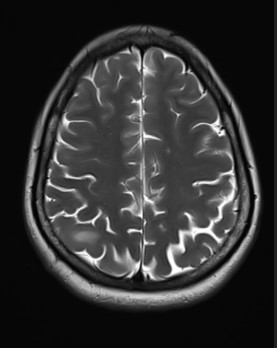

• A) Dilated right ventricle (yellow arrow) with prominent trabeculation, straightening of the interventricular septum, and a moderately dilated right atrium (black arrow) are evident.